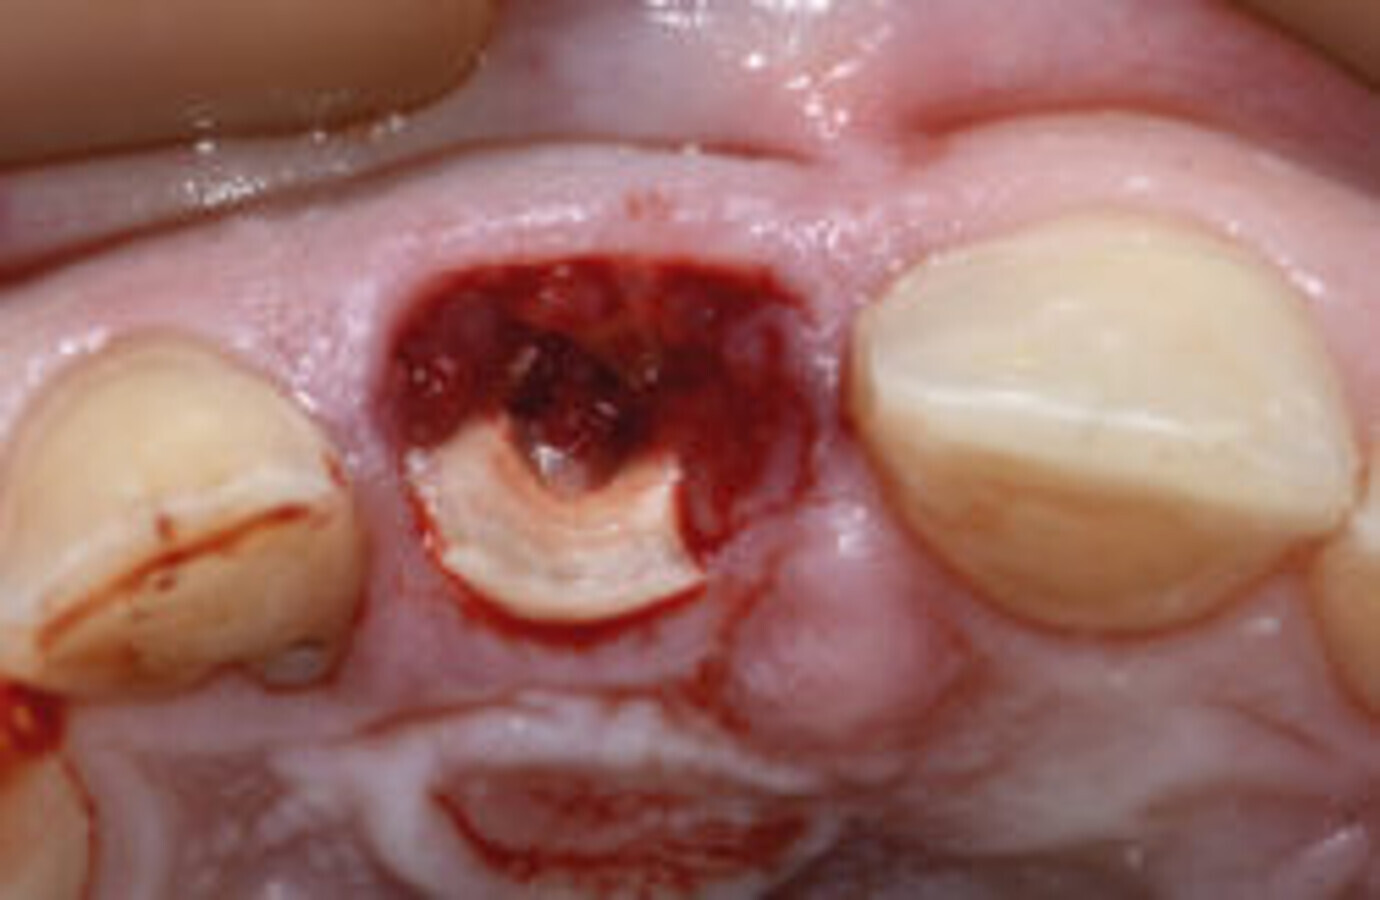

图1. 治疗前情况,考虑拔牙#11。

图9. #11骨折吸收处可见肉芽组织。

前期准备充分后,拔除患牙。患牙骨折吸收区明显可见肉芽组织(图9),使用Er:YAG激光治疗仪将其移除(H14型手持器械,欧洲之星Fotona;图10)。拔牙过程无创伤,创口干洁,可以行种植术(图11)。